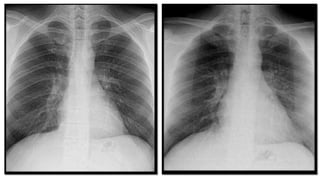

Rotation

• Patient in b is rotated to the left. The heart is appreciably in the left hemithorax, and the left side of the

chest is relatively elongated, as compared to the right. Note the opacity in the right lower chest field

(arrow). The reverse is true in e